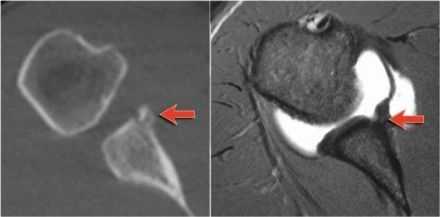

КТ-артрография, как правило, выполняется, когда нет возможности использовать МРТ. Метод позволяет получить схожую визуализацию разрывов связок и хряща, но дает низкую детализацию структуры мягких тканей по сравнению с МРТ.

(Слева) КТ-артрограмма тазобедренного сустава с остеоартритом (ОА), сагиттальный срез: визуализируется истончение хряща и субхондральные кисты в зоне с наибольшей нагрузкой.

(Справа) PD FS МР-артрограмма тазобедренного сустава с остеоартритом (ОА), сагиттальный срез: визуализируется полная утрата толщины хряща в верхней части с подлежащими субхондральными кистами. Истончение хряща вследствие остеоартрита (ОА) происходит в зонах нагрузки, в данном случае -в верхней и задней частях. Между этими участками визуализируется сохранившийся хрящ вертлужной впадины. (Слева) Аксиальная КТ-артрограмма, посттравматический остеоартрит (ОА) плечевого сустава у футболиста. Визуализируются неравномерная утрата хряща и множественные субхондральные кисты. Неровный контур сустава отражает наличие синовита.